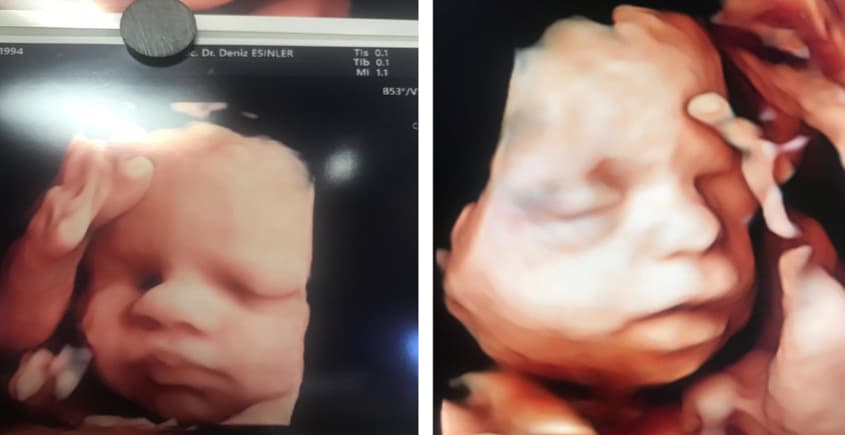

Gebeliğin 18-23. haftaları arasında yapılan, bebeğin tüm organlarının (beyin, kalp, böbrekler, eller, ayaklar vb.) detaylı olarak incelendiği radyolojik değerlendirmedir.

- Yüz profili, dudak ve damak yapısı

- Yüze ait sakatlıklar (örn: göz boşluğunun olmaması, yüzdeki yarıklar, dudak yarıkları vs.)